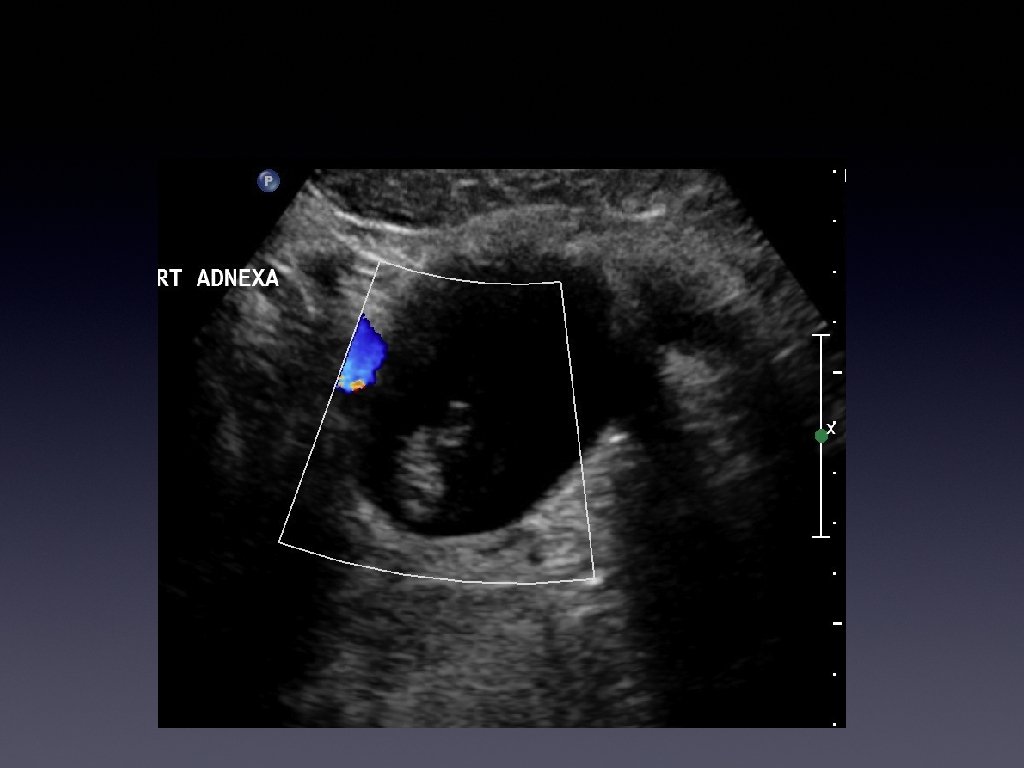

Few months later. . . • • • Patient continued to have pain Came

Few months later. . . • • • Patient continued to have pain Came back and this time tenderness was worse Bloods showed raised WBC count and CRP

Management • • • Patient was diagnosed with an infected hydrosalpinx She was taken

Management • • • Patient was diagnosed with an infected hydrosalpinx She was taken in for surgery Surgery revealed it was an appendiceal mucocoele

Learning points • • • Usually a cystic mass Variable internal echogenicity Devoid of

Learning points • • • Usually a cystic mass Variable internal echogenicity Devoid of septations Can have debris Not every tubular mass in the iliac fossa is ovarian in origin!!!!